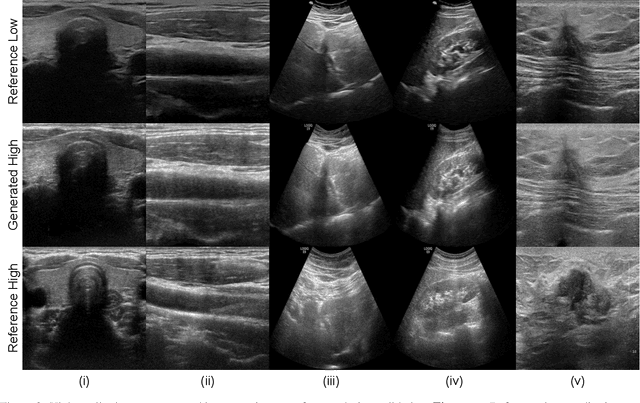

Abstract:Purpose: The objective of this work is to introduce an advanced framework designed to enhance ultrasound images, especially those captured by portable hand-held devices, which often produce lower quality images due to hardware constraints. Additionally, this framework is uniquely capable of effectively handling non-registered input ultrasound image pairs, addressing a common challenge in medical imaging. Materials and Methods: In this retrospective study, we utilized an enhanced generative adversarial network (CycleGAN) model for ultrasound image enhancement across five organ systems. Perceptual loss, derived from deep features of pretrained neural networks, is applied to ensure the human-perceptual quality of the enhanced images. These images are compared with paired images acquired from high resolution devices to demonstrate the model's ability to generate realistic high-quality images across organ systems. Results: Preliminary validation of the framework reveals promising performance metrics. The model generates images that result in a Structural Similarity Index (SSI) score of 0.722, Locally Normalized Cross-Correlation (LNCC) score of 0.902 and 28.802 for the Peak Signal-to-Noise Ratio (PSNR) metric. Conclusion: This work presents a significant advancement in medical imaging through the development of a CycleGAN model enhanced with Perceptual Loss (PL), effectively bridging the quality gap between ultrasound images from varied devices. By training on paired images, the model not only improves image quality but also ensures the preservation of vital anatomic structural content. This approach may improve equity in access to healthcare by enhancing portable device capabilities, although further validation and optimizations are necessary for broader clinical application.